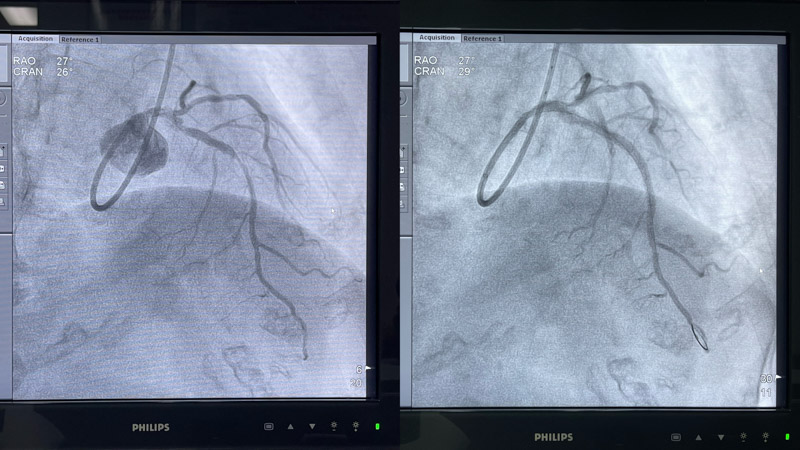

術中,心血管內科介入團隊將Shockwave C2 IVL 3.0*12mm 震波球囊置入前降支病變處,以4-6atm進行擴張后觸發8次10秒沖擊波,實施鈣化斑塊碎裂術,術后支架膨脹不全處明顯擴張,并順利于前降支近中段植入1枚支架。復查IVUS可見鈣化斑塊碎裂,支架貼壁和膨脹良好,血管擴張成形滿意,術后患者胸痛癥狀明顯好轉。

▲ 震波前、后造影對比圖